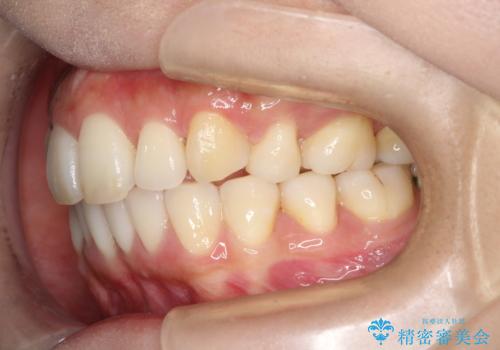

裏側装置で出っ歯の矯正治療

裏側からの矯正であったため、表側に比べて少し治療期間を要しました。

目立たずに矯正治療を終えることができ、満足していただけました。